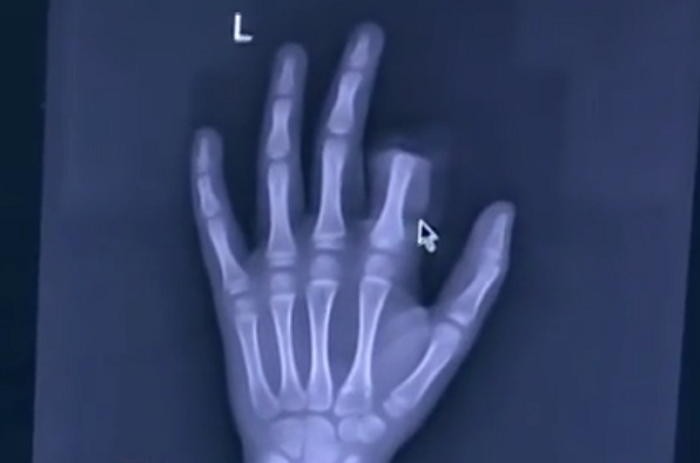

지난 6일(현지 시간) 중국 시나닷컴 등 외신들에 따르면 샤오펭(Xiaopeng, 11)은 전날 오전 중국 장쑤성 쑤저우의 자택에서 게임을 오래한다고 꾸중을 한 아빠의 말을 듣고 분노를 조절하지 못해 홧김에 왼쪽 검지손가락을 잘랐다.

아빠로부터 게임을 그만하라는 꾸중을 들은 샤오펭은 분노한 나머지 부엌에 있던 칼을 집어 들고 자신의 왼쪽 검지손가락을 내리쳤다.

절단된 손가락을 보고 크게 놀란 부모는 급히 구조대에 신고했고 병원으로 옮겨진 샤오펭은 3시간에 걸쳐 접합수술과 치료를 받고 무사히 퇴원했다.